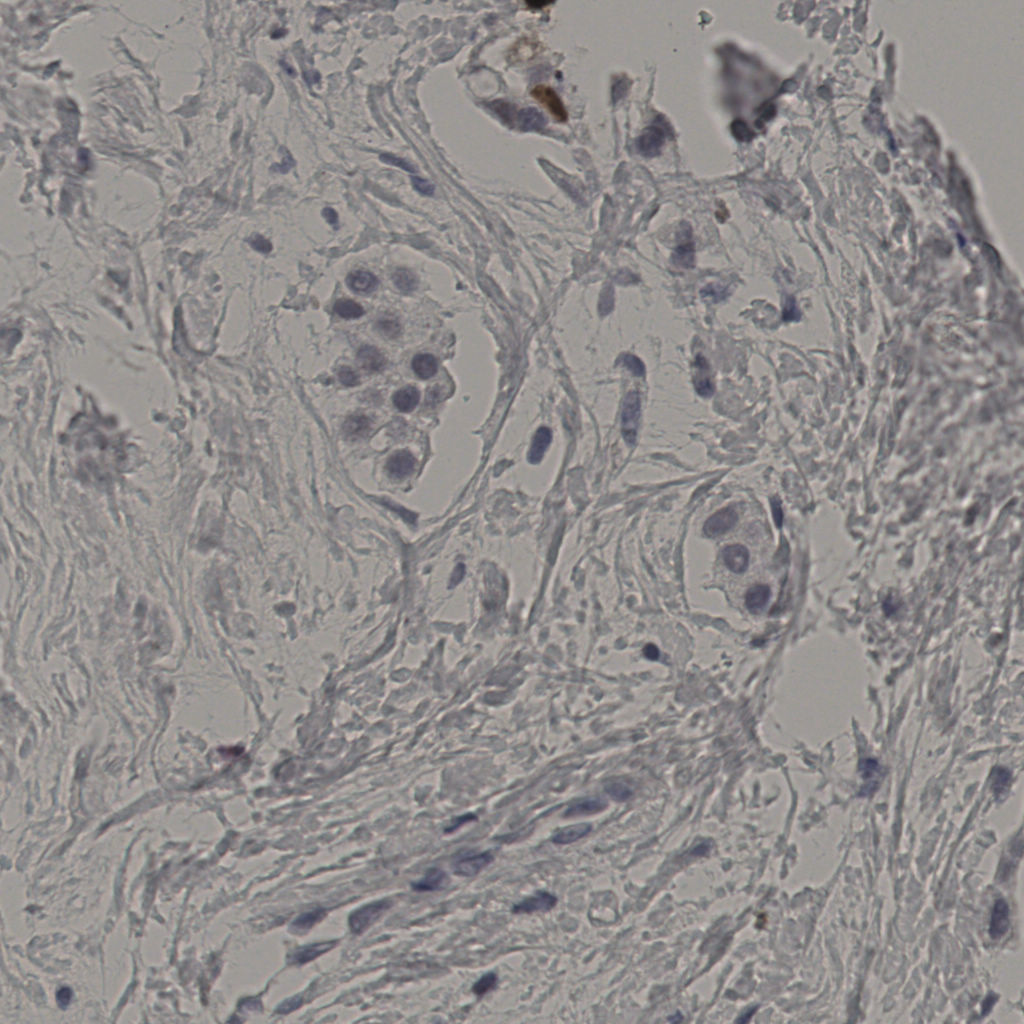

5.31%

Ki67 指数

阴 19502

阳 1093